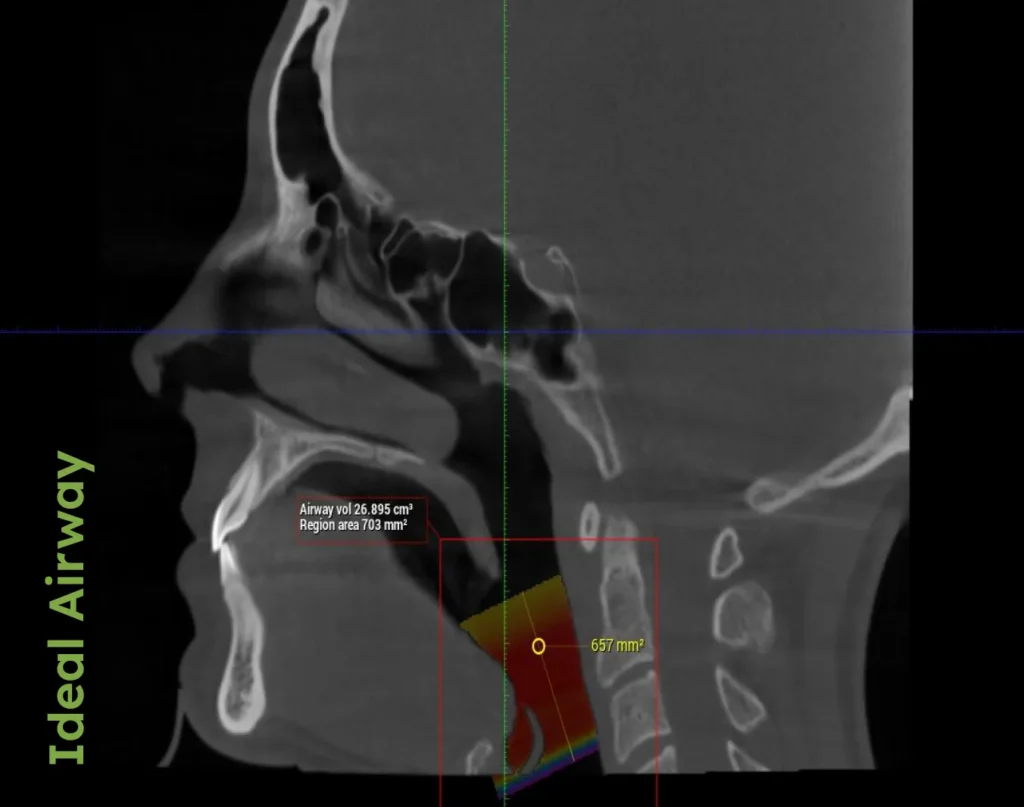

Our approach integrates various treatments tailored to each patient's unique needs, which encourage proper tongue positioning and nasal breathing, promoting optimal airway health.

• Palatal Expansion: Often the first stage in adult orthodontics for those with compromised airways, this technique helps to widen the upper jaw, improving nasal breathing and serving as a foundational step before aligning teeth.

By integrating traditional orthodontic techniques with a deep understanding of airway health, Dr. Porter ensures that every patient receives care that supports airway health. This holistic approach creates solutions that cater to the overall wellness of both children and adults, with a strong emphasis on early detection and intervention for lifelong benefits.